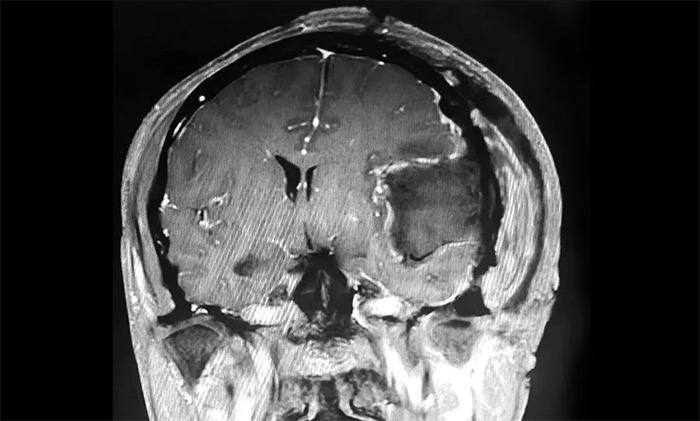

家人將其送往當(dāng)?shù)蒯t(yī)院,經(jīng)檢查,肩胛骨骨折。進(jìn)一步檢查頭顱CT,發(fā)現(xiàn)其左側(cè)額顳部團(tuán)塊狀高密度影,最大直徑約6.0公分(厘米)。病灶體積巨大,患者來(lái)到上海藍(lán)十字腦科醫(yī)院尋求進(jìn)一步治療。

入院后,患者收治于神經(jīng)內(nèi)科4A病區(qū)。完善針對(duì)性檢查后,經(jīng)多學(xué)科綜合會(huì)診,患者左側(cè)額顳部實(shí)性占位,最大直徑約6.0公分,體積如鴨蛋大小,考慮左側(cè)額顳部腦膜瘤。

▲ 腫瘤體積如鴨蛋大小